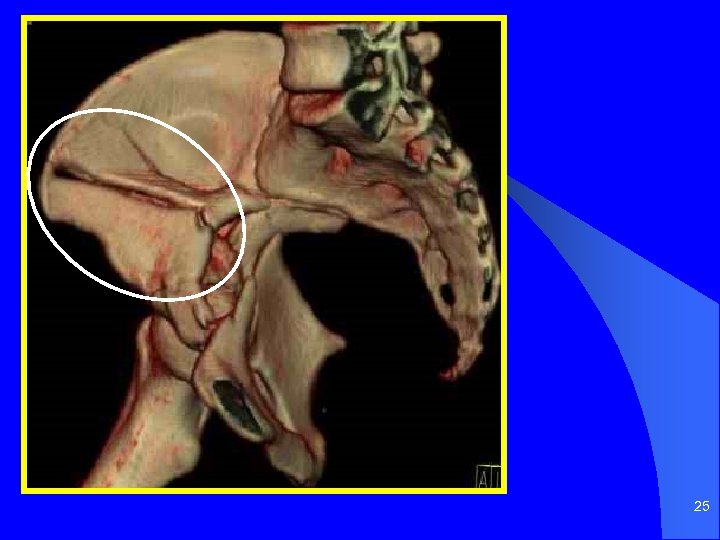

25